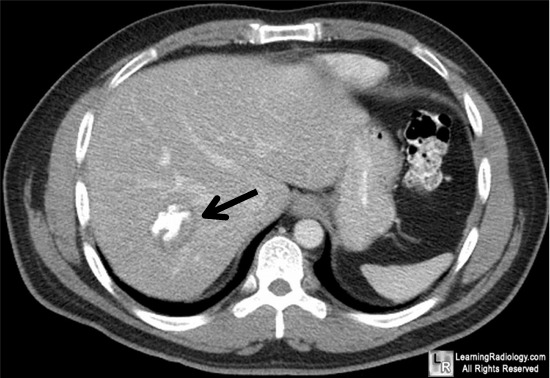

Calcifications In The Upper Abdomen

Per dL (13.88 mmol per L). Her liver function tests, amylase level, lipase level, complete blood and appear as a curvilinear rim of calcification in the wall of the aneurysm along the spine. Calcifications in the Upper Abdomen ... Access Content